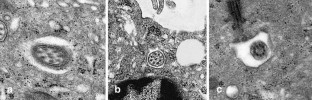

A chordoid glioma in the third ventricle was studied immunohistochemically and ultrastructurally. In this report, special attention is paid to the histogenesis in relation to the pathological appearance and unique anatomic location of this tumor. Light microscopic and immunohistochemical findings were similar to those reported previously. Ultrastructurally, microvilli were frequently seen, but three types of abnormal cilia were rarely observed. Basement membrane around the tumor cells and microvessels was extensive. Poorly to moderately developed intermediate (adherent) junctions were frequently seen. Resemblance of these ultrastructural features of the tumor to embryonic tanycytes suggests the tanycytic differentiation of chordoid glioma. Neuroradiologically, all of the previously reported cases of chordoid gliomas seem to arise in the anterior part of the third ventricular floor. This region includes the lamina terminalis, infundibular recess and median eminence, which corresponds to a tanycyte-rich area. These findings suggest a tanycytic origin of chordoid glioma.

Fig. 1.

Fig. 2.

Fig. 3.

Fig. 4.